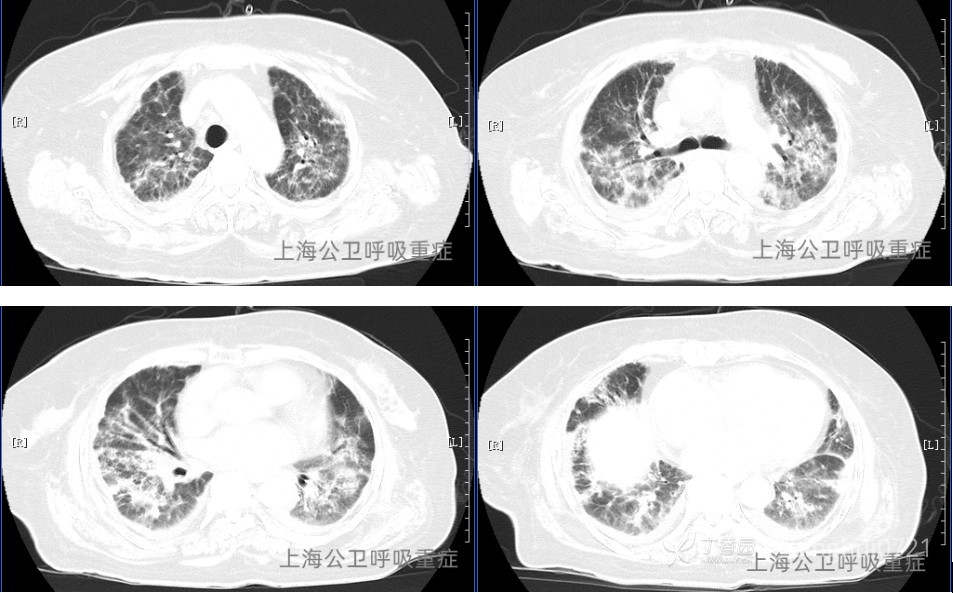

胸部CT:两肺感染,合并间质性水肿可能,两侧少量胸腔积液。纵隔淋巴结稍大。心脏增大。(见图1)CT两肺炎症较外院(07-19)相仿。

图1